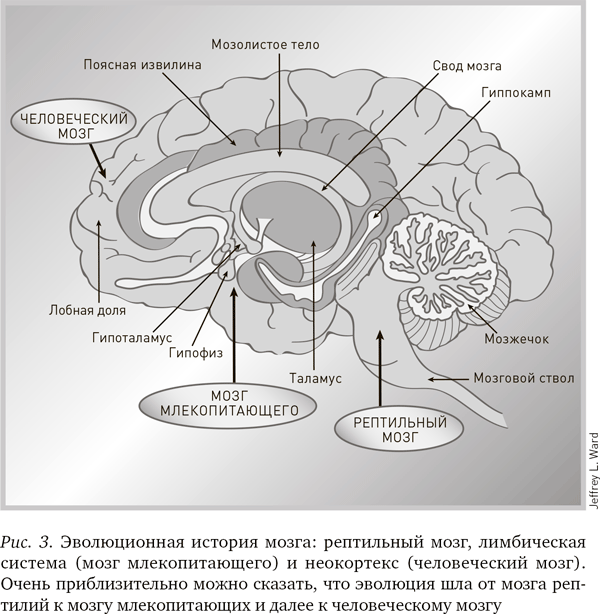

Чтобы разобраться в структуре мозга, которая кажется случайной, в 1967 г. доктор Пол Маклин из Национального института психического здоровья попытался рассмотреть эволюцию мозга с позиции теории Чарльза Дарвина. Он разделил мозг на три части. (Дальнейшие исследования показали, что эта модель нуждается в уточнении, но мы используем ее как грубый набросок для приблизительного объяснения общей структуры мозга.) Во-первых, он заметил, что задняя и центральная часть человеческого мозга, включая мозговой ствол, мозжечок и подкорковые узлы, почти идентична по строению мозгу рептилий. Эти структуры, известные как «рептильный мозг», – самые древние структуры мозга, – управляют фундаментальными функциями организма, такими как равновесие, дыхание, пищеварение, сердцебиение и поддержание кровяного давления. Кроме того, они контролируют такие поведенческие схемы, как драка, охота, спаривание и территориальность, необходимые для выживания и воспроизведения себе подобных. Рептильный мозг существует примерно 500 млн лет (рис. 3).

Но по мере того как наши предки эволюционировали от рептилий к млекопитающим, мозг усложнялся, развиваясь и формируя совершенно новые структуры. Так возник мозг млекопитающего, или лимбическая система, которая расположена возле центральной части мозга и окружает структуры рептильного мозга. Лимбическая система развита у животных, живущих социальными группами, в частности у человекообразных обезьян. Кроме того, она содержит структуры, определяющие эмоции. Динамика социальных групп может быть достаточно сложной, и лимбическая система необходима, чтобы различать потенциальных врагов, союзников и соперников.

Среди частей лимбической системы, управляющих жизненно важными для социальных животных поведенческими схемами, можно назвать:

• гиппокамп – это ворота памяти, где кратковременные воспоминания преобразуются в долговременные. Название этой области переводится как «морской конек», что объясняется ее странной формой. Повреждение гиппокампа лишает человека способности сохранять воспоминания. Он навсегда остается пленником настоящего времени;

• мозжечковая миндалина – место, где эмоции, в первую очередь страх, регистрируются и формируются. Название тоже дано по форме;

• таламус – это что-то вроде релейной станции, которая собирает сенсорную информацию от мозгового ствола и направляет ее в разные участки коры. Название означает «внутренняя полость»;

• гипоталамус – этот орган регулирует температуру тела, суточный ритм, голод, жажду и некоторые аспекты размножения и наслаждения. Располагается он под таламусом – отсюда и название.

Наконец, у нас имеется третья, самая молодая область мозга млекопитающих – кора, внешний слой мозга. Самая поздняя в эволюционном отношении структура коры головного мозга – неокортекс (новая кора), который управляет когнитивным поведением. Лучше всего эта структура развита у человека: она составляет 80 % массы мозга, но при этом представляет собой лист толщиной с салфетку. У крыс неокортекс гладкий, а у людей он сильно извит; благодаря этой извитости в черепе человека умещается лист большой площади.